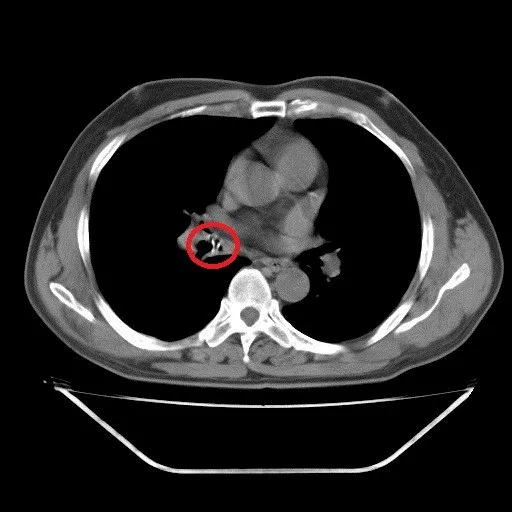

Dị vật ở lòng phế quản trung gian phổi phải qua hình ảnh chụp cắt lớp vi tính

Tại Khoa Nội tổng hợp, bệnh nhân Đ. được các bác sĩ cho làm các xét nghiệm cần thiết nhưng không phát hiện ra vấn đề gì. Lúc này các bác sĩ đã hỏi tiền sử của bệnh nhân trong thời gian qua thì nghi ngờ bệnh nhân bị mắc dị vật, đồng thời tiến hành chụp CT lồng ngực, qua đó phát hiện ở lòng phế quản trung gian phổi phải có dị vật.